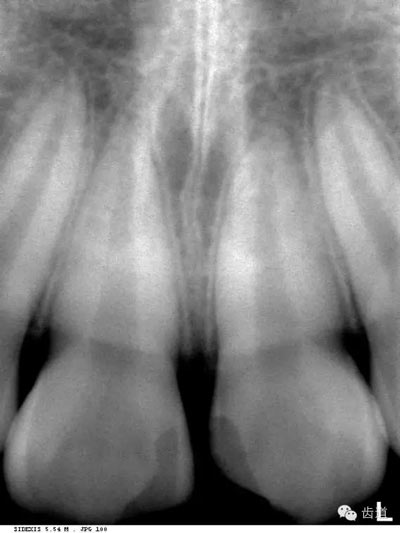

是上下頜骨包圍牙根的突起部分,又稱牙槽突或牙槽嵴。X線片上牙槽骨所顯示的密度較牙低。上牙槽骨的密質(zhì)骨薄,松質(zhì)骨多,即骨小梁數(shù)目多,相交處呈密度高的點(diǎn)狀影像,骨髓腔則呈點(diǎn)狀密度低的影像,固上牙牙槽骨的骨小梁結(jié)構(gòu)X線片上呈顆粒狀影像;

牙槽骨:下牙槽骨密質(zhì)骨厚而松質(zhì)骨少,骨小梁多呈水平方向排列,骨髓腔呈三角形和大小不等的圓形密度低的影像,所以下牙槽骨的骨小梁結(jié)構(gòu)呈網(wǎng)狀結(jié)構(gòu)

即固有牙槽骨,是牙槽骨的內(nèi)壁,圍繞牙根,骨質(zhì)致密而薄,X線片上顯示為包繞牙根的連續(xù)不斷的密度高的線條狀影像。

是介于牙槽窩和牙骨質(zhì)之間的結(jié)締組織。牙周膜的厚度一般在0.15~0.38mm之間。X線上顯示為包繞牙根連續(xù)不斷的密度低的線條狀影像,其寬度均勻一致